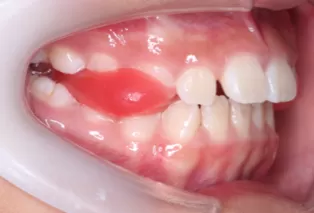

Photos intra-orales après traitement